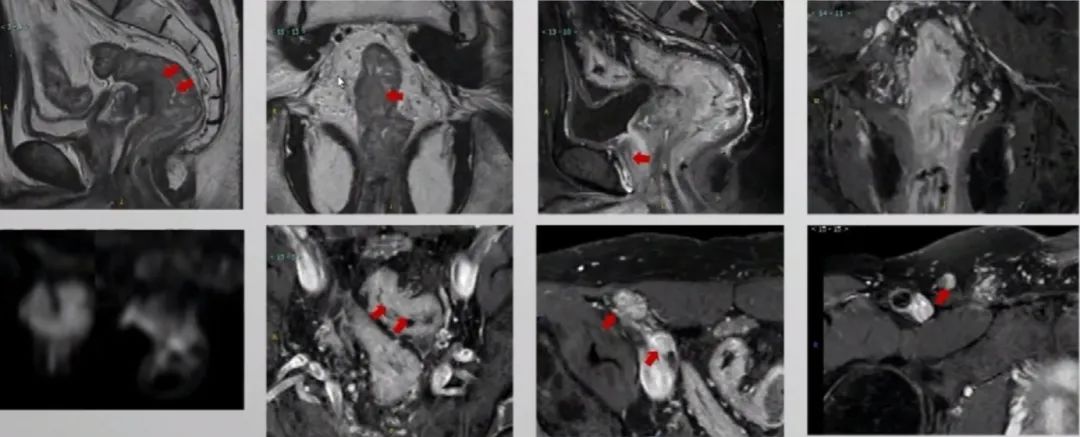

2019.1.16盆腔增强MR

1. 上段直肠癌,MR分期拟T4bN0M1,MRF(+),EMVI(-);

2. 乙状结肠癌,MR分期拟T3aN0M1。